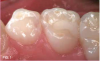

Case 2. This 2-year-old boy had mesial caries lesions of his maxillary central incisors associated with chronic plaque accumulation and lack of tooth brushing or flossing by the parents (Figure 5 and Figure 6). The parents, who were given extensive instructions to remedy the oral hygiene problem, consented to SDF application despite the black discoloration. They related that they not only wanted to avoid a repair appointment for the child, but they also liked the idea that traditional restoration could be delayed until he was older and could more easily tolerate treatment. Three months after initial SDF application, the solution was reapplied (Figure 7).

Fig 7. 3 months after SDF application, before renewed application.

Fig 7